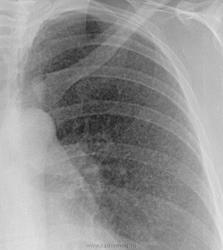

Редко приходится смотреть обычные рентгенограммы, но рискну предположить, что в первом случае ретикулярные изменения, а во втором - нодулярные.

По первой пусть будет альвеоларный протеиноз или какая-нибудь лимфогенная диссеминация, по второй - по типу центрилобулярных очагов, хаотично расположенных - гиперчувствительный пневмонит, тубер, ранние стадии гистиоцитоза, мтс тоже, но в меньшей степени.

Наблюдения, конечно интересные. Представлен синдром, так называемой "диссеминации", и это правильно. При употреблении термина "диссеминация", мы однозначно, подразумеваем "очаговую диссеминацию", т.е. наличие скиалогии, основным компонентом, которой является очаг. А эти иллюстрации зародили в душе моей сомнения, если в первом случае "очаговая компонента" не вызывает сомнений - мелкоочаговые тени, то во втором случае, явно не очаг, а как Вы правильно заметили "нодулюс", следовательно, термин "нодулярная диссеминация", имеет право на жизнь?